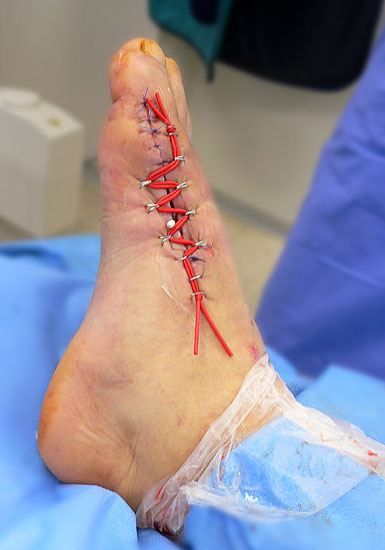

Wundheilungsstörung und Infekt

Zeichnet sich eine Wundheilungsstörung oder ein Infekt ab, hat sich unseren Händen ein aggressives Vorgehen bewährt. Die Antibiotika-Therapie erfolgt nach den allgemeinen Regeln für Knochen- und Weichteilinfekte. Lässt sich aufgrund der Weichteilschwellung nach operativer Revision ein primärer Wundverschluss nicht erreichen, kann durch eine mehrtägige Vakuumbehandlung der Wundgrund konditioniert werden 37. Nach Ausheilung des Infektes können Defektzonen bis ca. 4 cm durch eine Dermatotraktion sekundär verschlossen werden (Abb. 28). Hierzu werden Klammern in den Wundrand gesetzt durch welche ein elastischer Vessel-Loop eingezogen wird (Abbildung 29). Beim täglichen Verbandswechsel wird sukzessive die Vorspannung erhöht. Durch die gleichmäßige Traktion über mehrere Tage lässt sich so die Wunde verschließen. Bei mittelgroßen Defekten kann nach Konditionierung des Wundgrundes der Defekt mit Spalthaut verschlossen werden. Die großen Sehnenflächen am Fußrücken limitieren allerdings diese Technik 38. Auf freiliegen Sehnen gelingt es normalerweise nicht einen ausreichenden Granulationsrasen zu erzeugen, der die Basis für eine erfolgreiche Spalthauttransplantation bildet. In solchen Fällen, sowie bei größeren Defekten ist zeitnah die Mitbetreuung des Patienten durch einen plastischen Chirurgen sinnvoll 39. Mithilfe gefäßgestielter Lappen lassen sich auch großflächige Defekte kosmetisch zufriedenstellend verschließen (Abbildung 28).